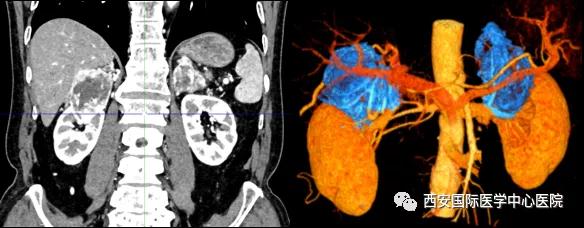

7月15日,西安國(guó)際醫(yī)學(xué)中心醫(yī)院泌尿外科楊增悅教授團(tuán)隊(duì)成功完成“機(jī)器人輔助根治性右腎、右腎上腺部分切除 左腎上腺切除 腎門(mén)淋巴結(jié)清掃術(shù)”。此臺(tái)手術(shù)涉及三個(gè)器官:右腎切除、右側(cè)腎上腺轉(zhuǎn)移瘤切除(保留部分正常腎上腺組織)、左腎上腺切除,并且清掃了腎門(mén)淋巴結(jié)。

患者一家慕名前來(lái)到西安國(guó)際醫(yī)學(xué)中心醫(yī)院找到楊增悅教授。楊增悅教授仔細(xì)看完患者的之前的影像學(xué)及病理資料后,診斷為:右腎透明細(xì)胞癌(T4N1M1);并安排他住院。而后,主管醫(yī)生及時(shí)為他完善了術(shù)前檢查及評(píng)估。7月15日,在麻醉手術(shù)中心柴偉主任、王彬榮副主任、李娟護(hù)士長(zhǎng)、李瑞剛護(hù)士長(zhǎng)及全體麻醉手術(shù)中心團(tuán)隊(duì)的有力保障下,成功完成了這臺(tái)“大”手術(shù)。

手術(shù)由楊增悅教授主持,舒濤主治醫(yī)師、王東主治醫(yī)師主刀,黃怡醫(yī)師、王平醫(yī)師協(xié)助完成。由于第四代達(dá)芬奇機(jī)器人更加靈活和精準(zhǔn)的特性,手術(shù)全程順利,尤其是完全精準(zhǔn)的“解鎖”了右腎動(dòng)脈和右腎靜脈的數(shù)十根交互纏繞的分支血管。術(shù)后患者麻醉恢復(fù)后生命體征平穩(wěn),順利返回泌尿外科普通病區(qū)進(jìn)一步康復(fù)。